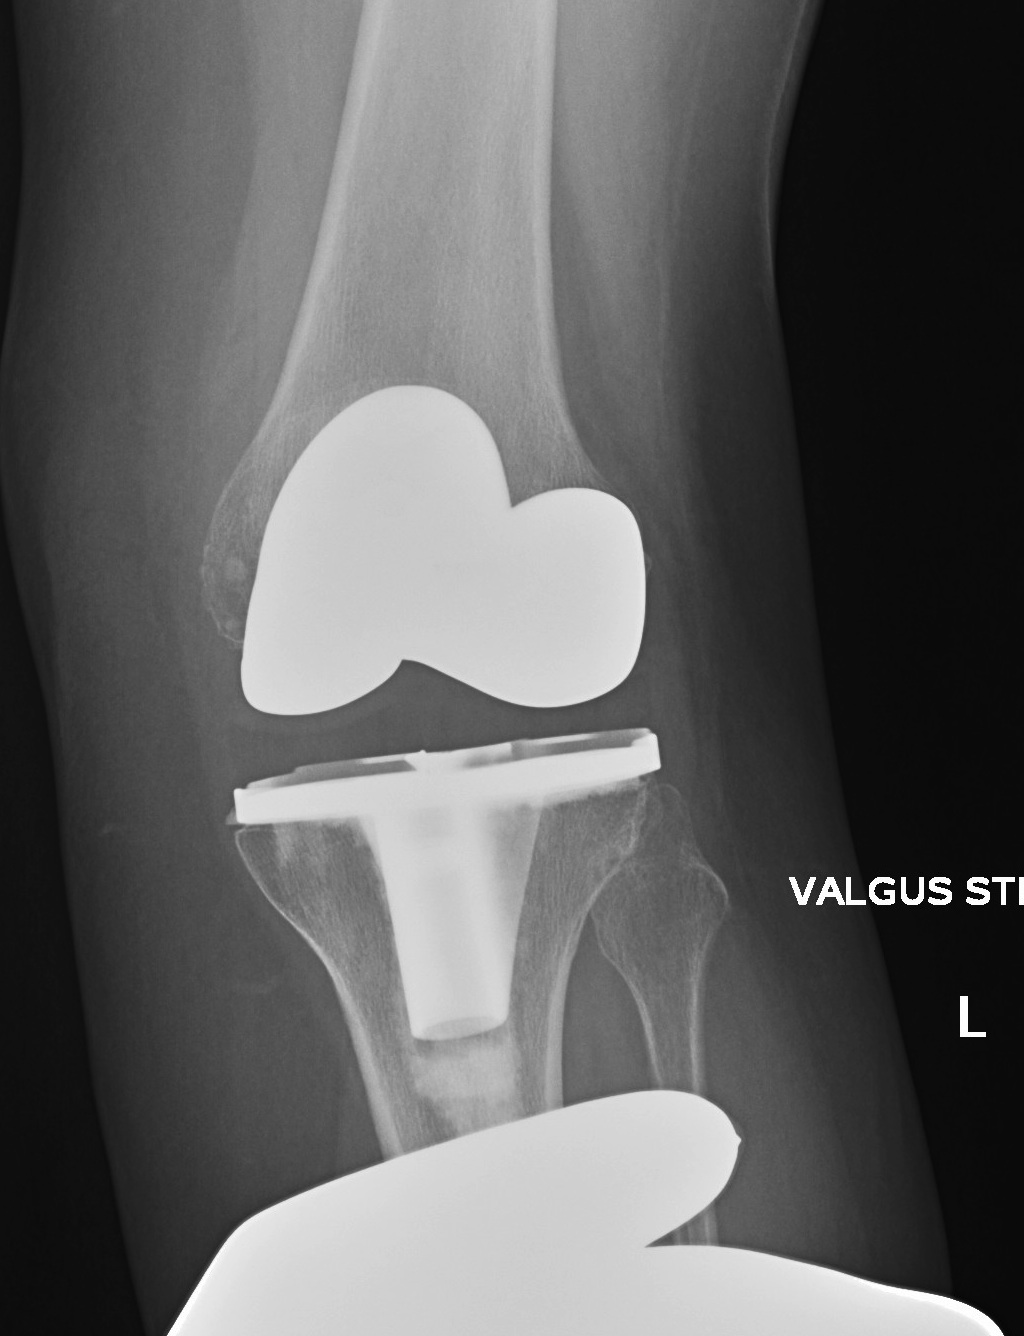

2. Varus Valgus Instability

Varus-Valgus instability

C. Insufficient poly / loosening over time

Diagnose

- equal varus and valgus instability

Management

- increase poly thickness